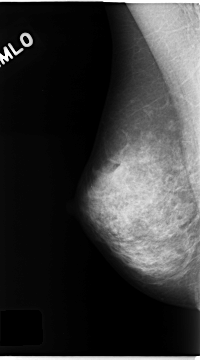

C_0142_1.LEFT_MLO

RIGHT_MLO LINES 4672 PIXELS_PER_LINE 2600 BITS_PER_PIXEL 12 RESOLUTION 50 NON_OVERLAY